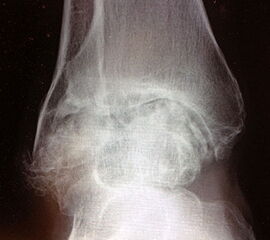

Bildgebung: konventionelles Röntgen: OSG 2 Ebenen belastet, Fuß seitlich im Stehen. Bedarfsweise Beinachsaufnahmen im Stehen; Bedarfsweise Broden Aufnahmen und Saltzmann-View. MRT: Bedarfsweise bei Synovialitis, ausgeprägter ossärer Zystenbildung und zur Beurteilung der Mitbeteiligung des USG. CT: Bedarfsweise bei ossärer Defektbildung, bei komplexer Achsfehlstellung oder Deformierung ggf. als 3-D-Rekonstruktion Sonografie: Nicht erforderlich.

Folgezustände nach fehlverheilten Sprunggelenkfrakturen und Sprunggelenkluxationsfrakturen